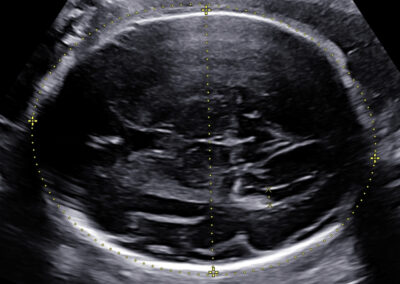

Dear future mother, we provide both basic and specialized ultrasound scans in pregnancy. We use Samsung’s state-of-the-art ultrasound systems and all our doctors are holders of Fetal Medicine Foundation certificates for all types of ultrasound examinations in pregnancy. We follow FMF protocols for fetal examinations and combine 2D with 3D ultrasound scan and assess even subtle anatomical details in order to obtain as precise a result as possible. Throughout the scan, we will keep you informed about the parts of fetal anatomy displayed on the screen. After the scan we will explain to you the results, prognosis and possible further management.

Early pregnancy scan Nuchal translucency scan in 1st trimester Anomaly scan in the 2nd trimester Fetal wellbeing scan in the 3rd trimester